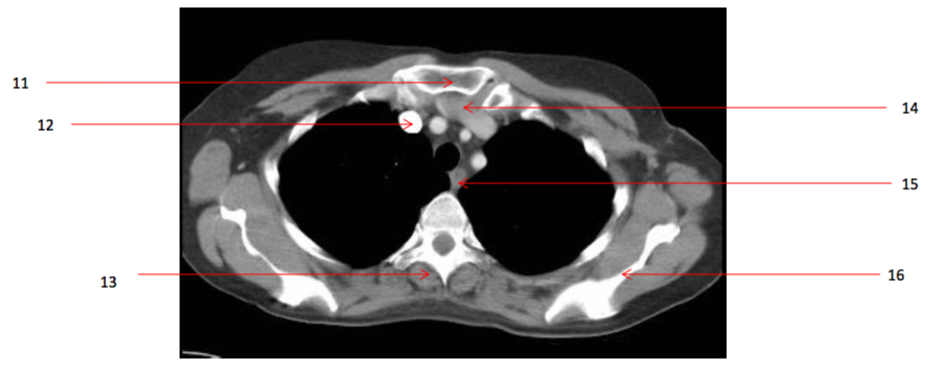

Number 13?

Rt erectae spinae muscle

Number 16?

Lt scapula

Q

A

Lt brachiocephalic vein

Number 11?

Sternum (manubrium)

Number 12?

Rt brachiocephalic vein

Number 15?

oesophagus